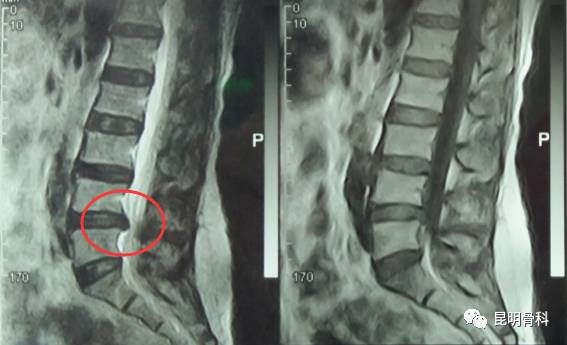

▲光学影像资料显示腰椎间盘突出▼

经多方打听之后,她慕名求助昆明骨科医院。通过诊断后,赵女士被确诊为“腰4-5椎间盘突出。”骨病科张鑫主任在仔细研究了腰椎CT及核磁共振片后,结合病情实事求是地告诉她,椎间盘突出比较严重,且还有椎管狭窄、侧隐窝狭窄等,已经明显压迫到神经。现在用保守治疗已无效果,只有把压在神经上的椎间盘取出来,才能从根本上解决问题,而昆骨微创/椎间孔镜就是较好的选择。